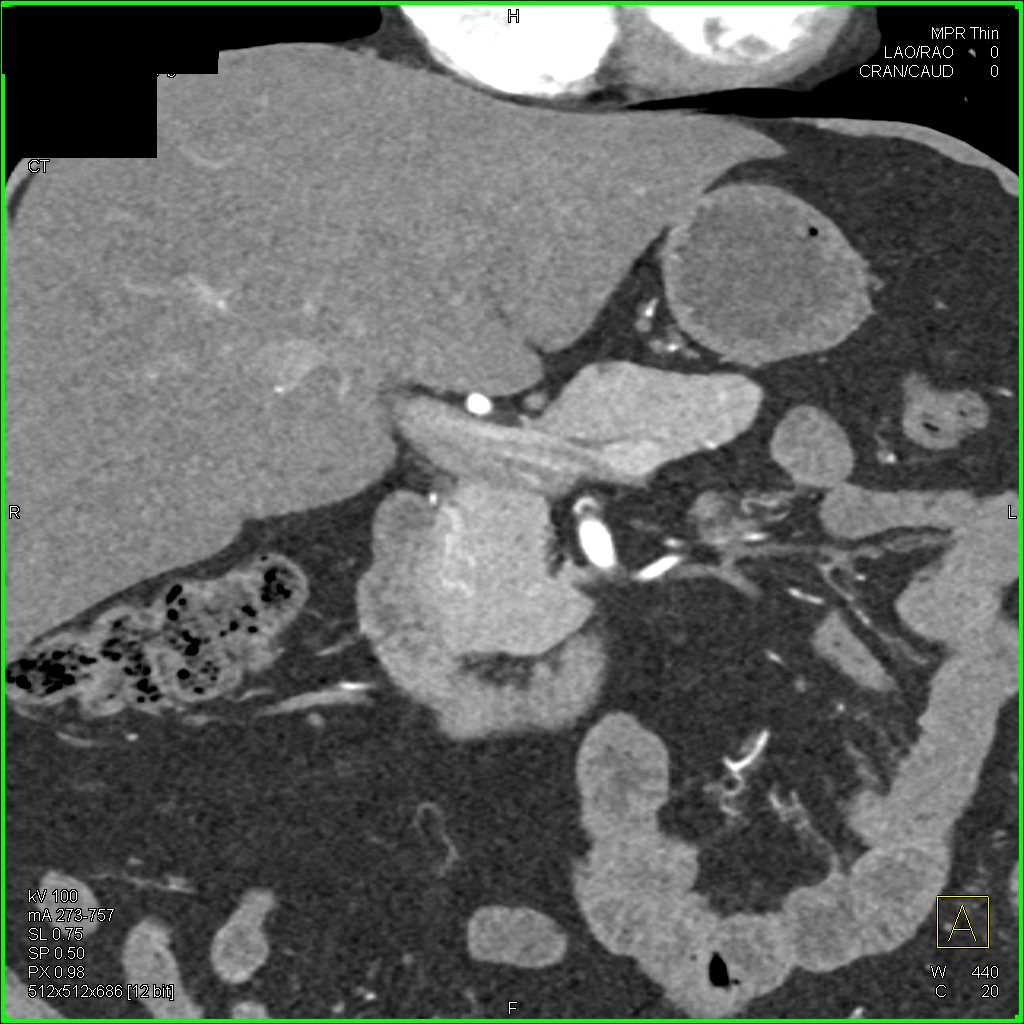

Carcinoma Pancreas with Dilated Pancreatic Duct